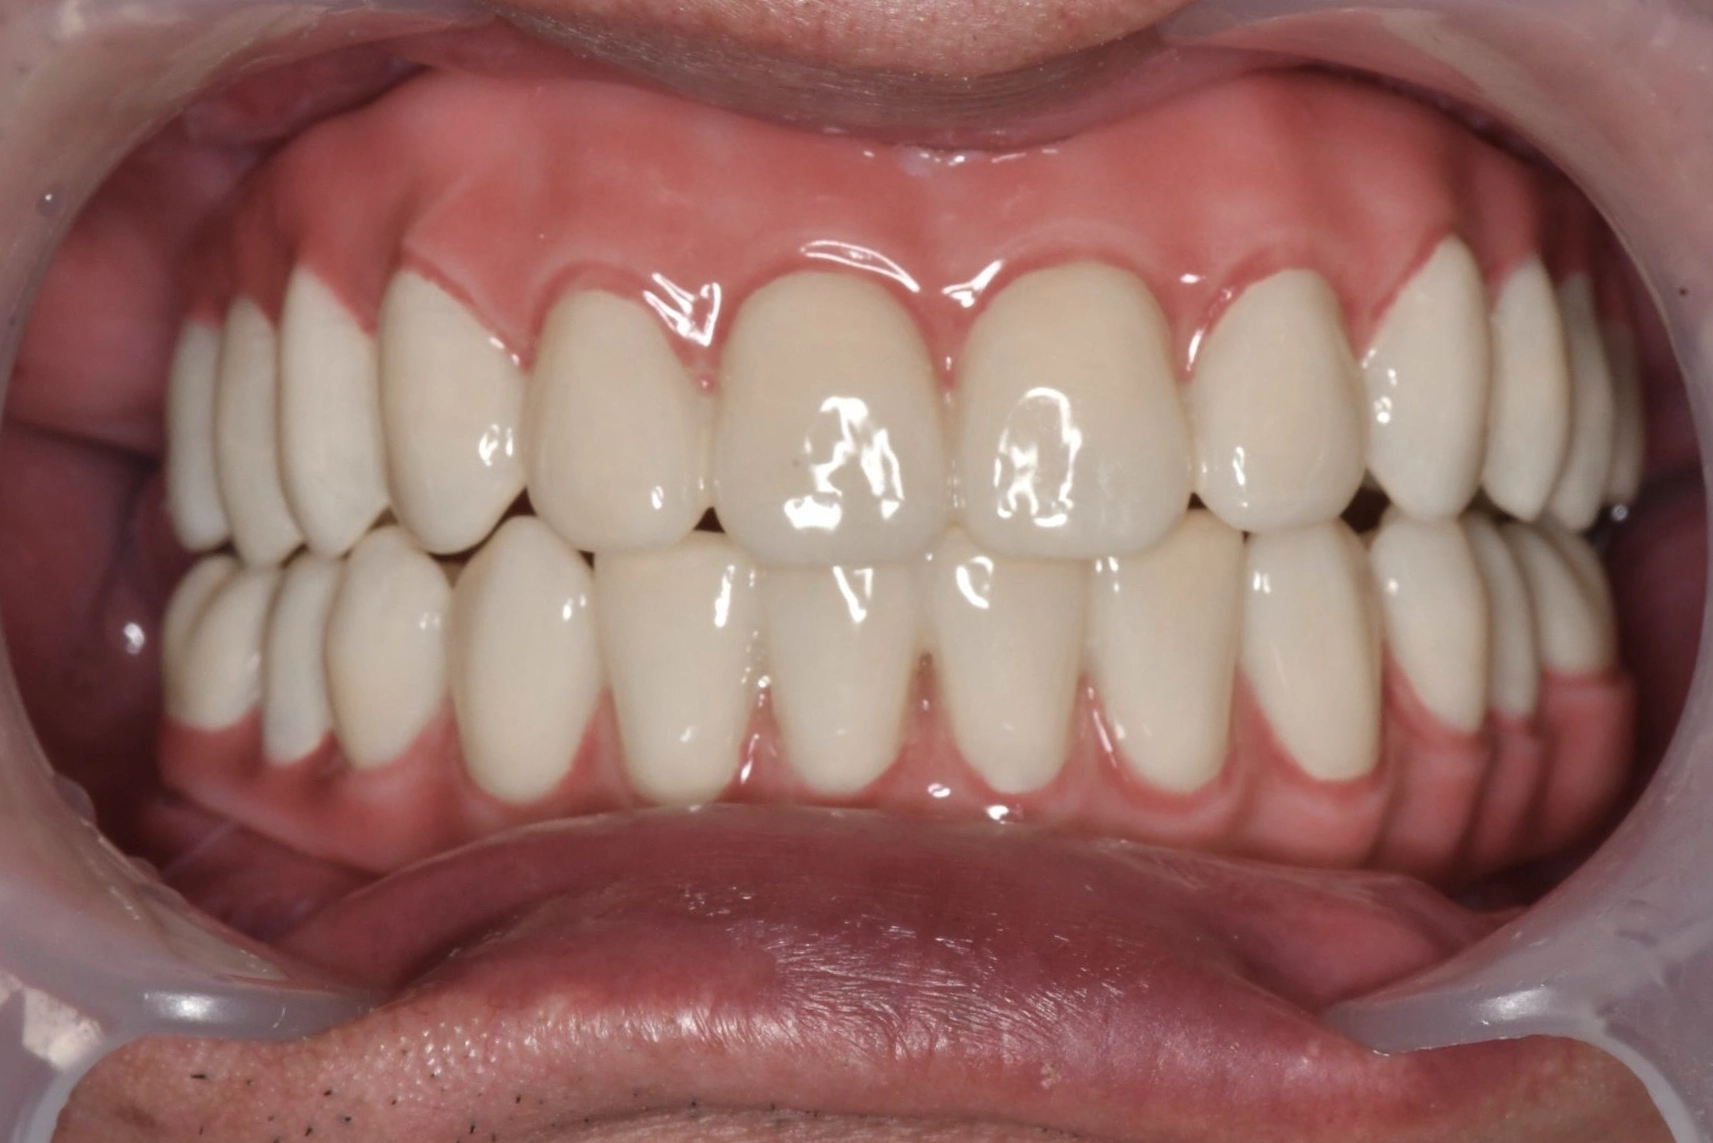

術後

手術は計画通り進行し、術後の仕上がりにもとても満足しています。

長年苦しめられた義歯による痛みや不自由さから解放され、食事を楽しめるようになることが楽しみです。美しい見た目になったのでマスクを外して過ごせるようになることも嬉しいです。自分と同じように歯の悩みで苦しむ方にぜひ勧めたいです。